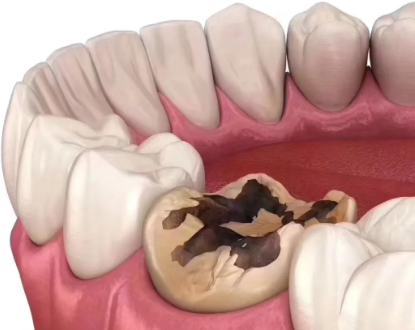

临床常规根管治疗通常需2~3次就诊,相邻两次复诊间隔1~2周,部分感染较轻的患者可通过2次就诊完成全程治疗。就诊次数和间隔并非固定,需结合牙齿感染程度、根管复杂程度调整:急性牙髓炎首次仅做开髓引流缓解疼痛,1~2周后复诊完成后续根管清理、消毒与填充;慢性根尖周炎等重症患者可能需3次及以上复诊,每次间隔仍控制在1~2周,确保炎症充分消退。治疗完成后还需做牙冠保护患牙,患者应遵医嘱复诊并做好口腔护理。